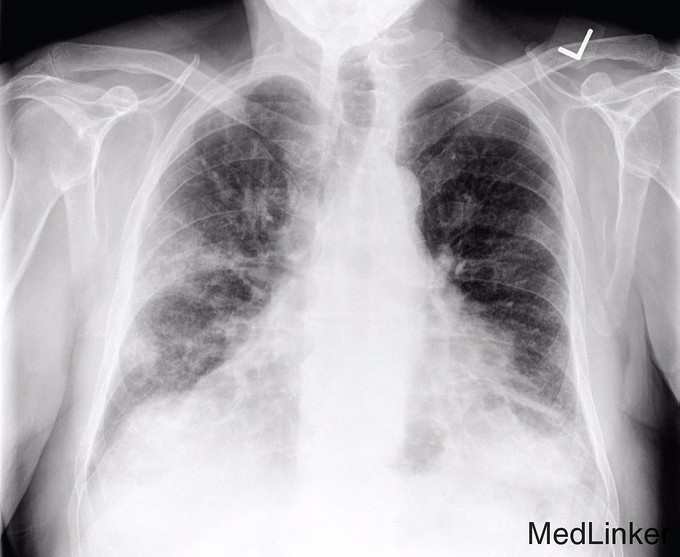

入院前5-6周胸部X线示双侧肺片団影(图1),怀疑为社区获得性肺炎,给予阿奇霉素和莫西沙星,症状无明显改善。入院后体检发现患者有中度呼吸窘迫,血压171/88 mmHg,血氧饱和度86%。查体:患者有双侧哮鸣音及啰音,余未查见特殊。白细胞计数正常,胸部X线提示右下肺和左肺中央显著地恶化(图2)。胸部CT提示弥漫性肺病变,右侧少量胸腔积液,胸内,颈下淋巴结肿大(图3)。